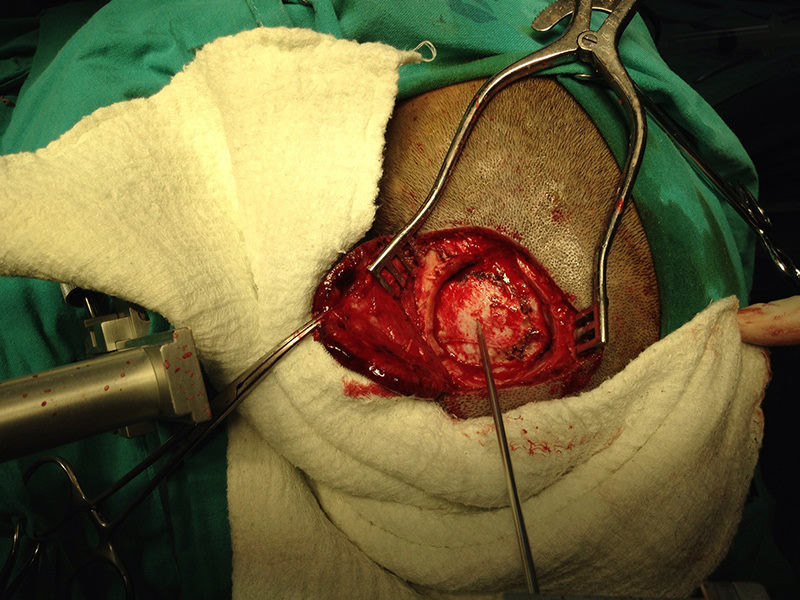

Casos Neuroloquirúrgicos

Envíado por Dr. Ruben Eduardo Amaya Contreras